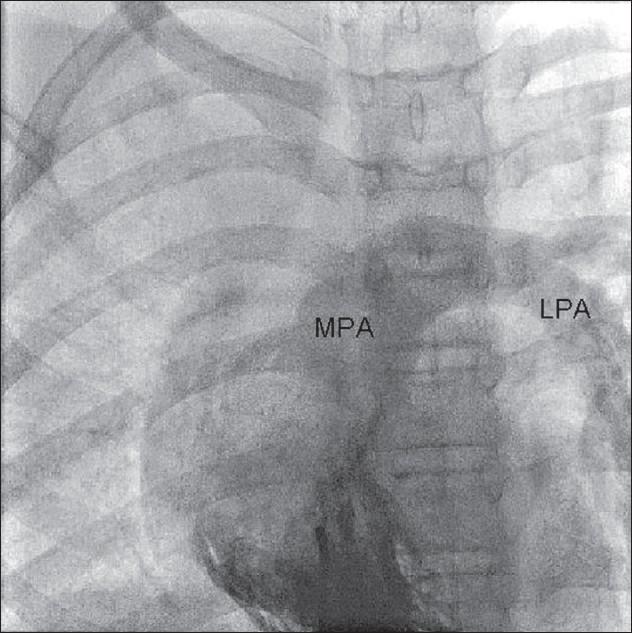

Scimitar syndrome is a rare congenital disorder. It has a varied presentation. In adult life, it usually presents either as recurrent chest infection and/or exertional dyspnea. Pulmonary artery hypertension and hemoptysis both are uncommon features of this syndrome in adult life.

弯刀综合征是一种罕见的先天性疾病。其表现多样。在成年期,它通常表现为反复的胸部感染和/或劳力性呼吸困难。肺动脉高压和咯血在成年期都是该综合征不常见的特征。